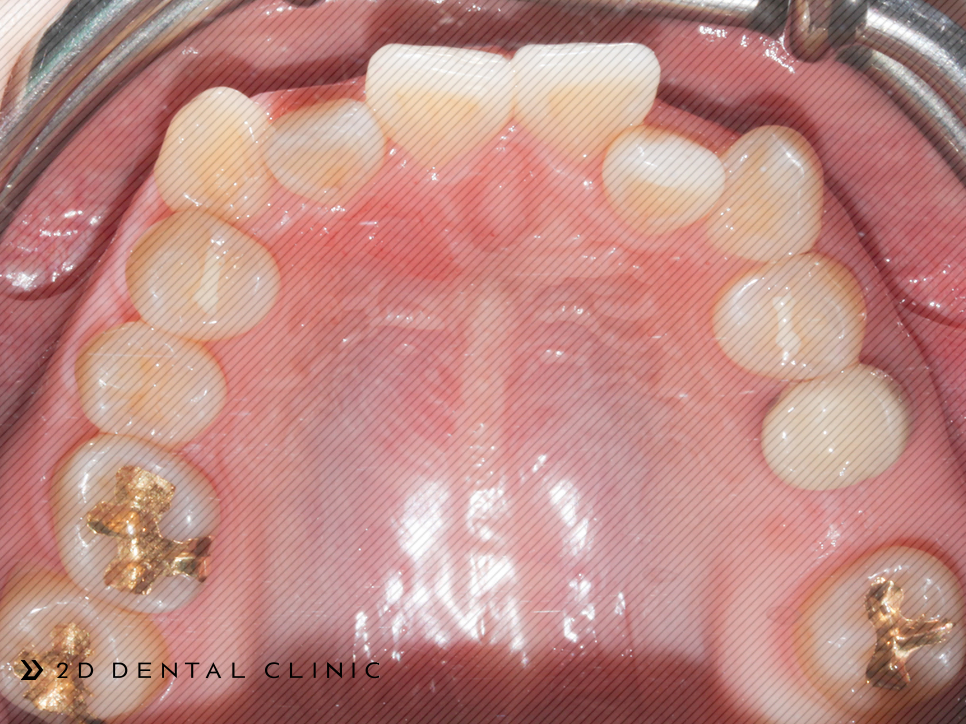

전체 교정인 클리피씨로 진행되었고 상악의 양쪽의 제1소구치를 발치하였습니다. 제2 대구치는 미니스크류로 당겨드렸고요.

전체적인 크라우딩의 개선

교정기간은 1년 반이 소요되셨답니다~ 전체적인 크라우딩이 개선되고 치아 배열이 고르게 개선되었습니다.